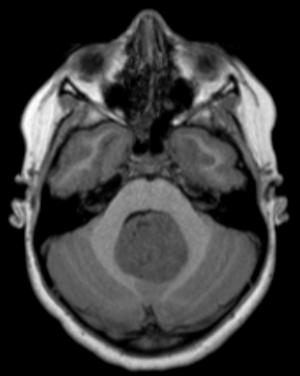

Image IQ Quiz: Pediatric Patient Presents with Double Vision

Pediatric patient presents with double vision. What is the most likely diagnosis?